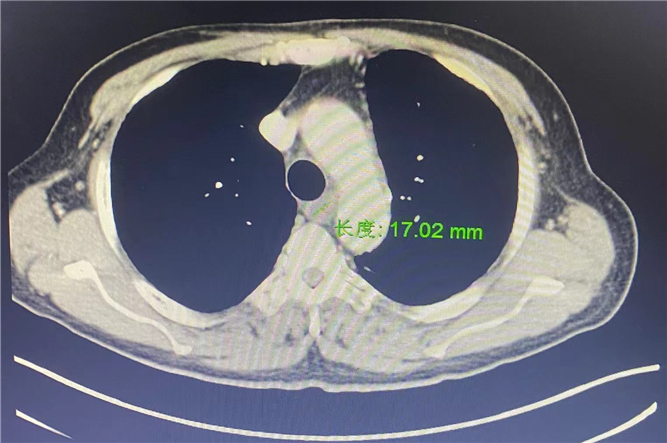

治療3周后:17.02mm

放療的同時,化療也同時跟進。3周后,癥狀緩解,病灶也縮小了。一個抗癌治療周期結(jié)束后,順利出院。隨訪的半年來,張大爺?shù)纳眢w、精神狀況都很好,吃飯吞咽也順暢了。